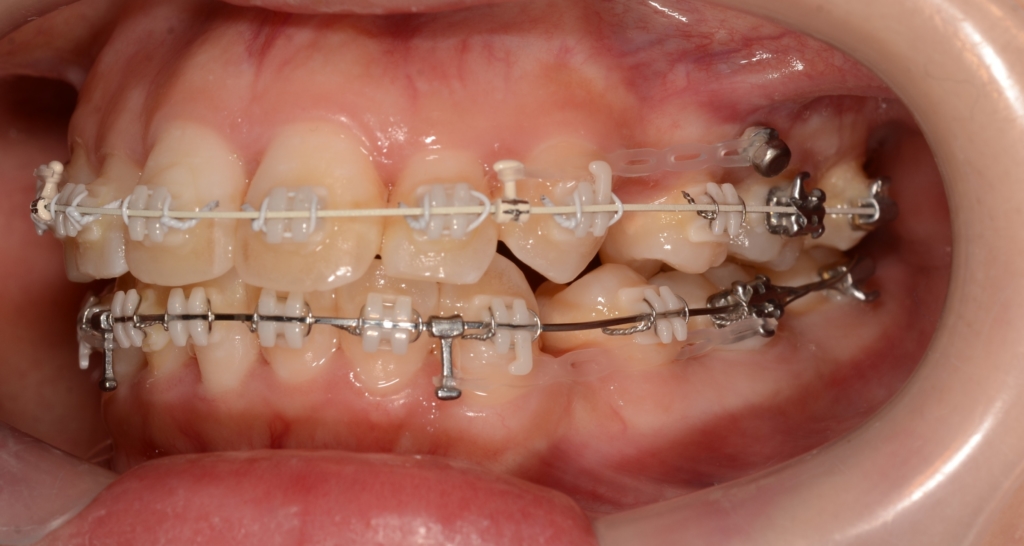

【隙間の閉鎖へ】

上下とも前歯はきれいに並びましたので、次のステップに移ります。

「口元がちょっとでも引っ込んで欲しい!」という」希望があったので、アンカースクリューを併用して治療を進めることにしました。

治癒期間を待ったうえで、前歯を積極的に引っ込めながら、残る抜歯スペースを閉じます。